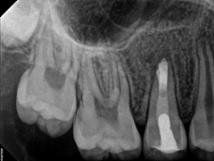

Every tooth has different numbers of roots and canal systems. With the help of magnification and high tech equipment, Dr. Jung can locate and treat the canals including MB2 on upper molars and MM on lower molars.